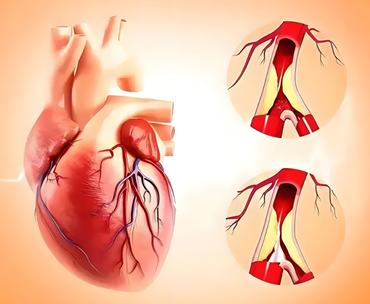

在医学里,心脏是一个孤零零的器官,但心血管系统却是一个由心脏、每一层动脉、庞大的毛细血管网络,以及一层层静脉组成的循环结构。这看似是个小问题,实际上,却是一个关乎心血管医学最底层的核心架构的大问题。

心血管系统是个什么样的网络呢?让我们在这个网络里来趟说走就走的旅行。我们的血液会从左侧的心室射出,经过主动脉、大动脉、中动脉、小动脉,最后到达只允许人体最小的细胞单行通过的毛细血管。它只有一根头发丝的十分之一那么细。

毛细血管将氧气和养分一个不落地带给全身37.2万亿个细胞,然后再从毛细血管回收到小静脉、中静脉、中央静脉,最后回到右侧的心房,流到右侧的心室,随着心脏收缩,从右心室射出的血液经过肺的各层动脉、毛细血管、各层静脉,将氧气带回到左侧心房,流到左侧心室。

它用了一个层递式的结构,从心脏开始,大动脉分出若干个中动脉,每个中动脉再分成若干小动脉,小动脉又分出更为庞大的毛细血管网。